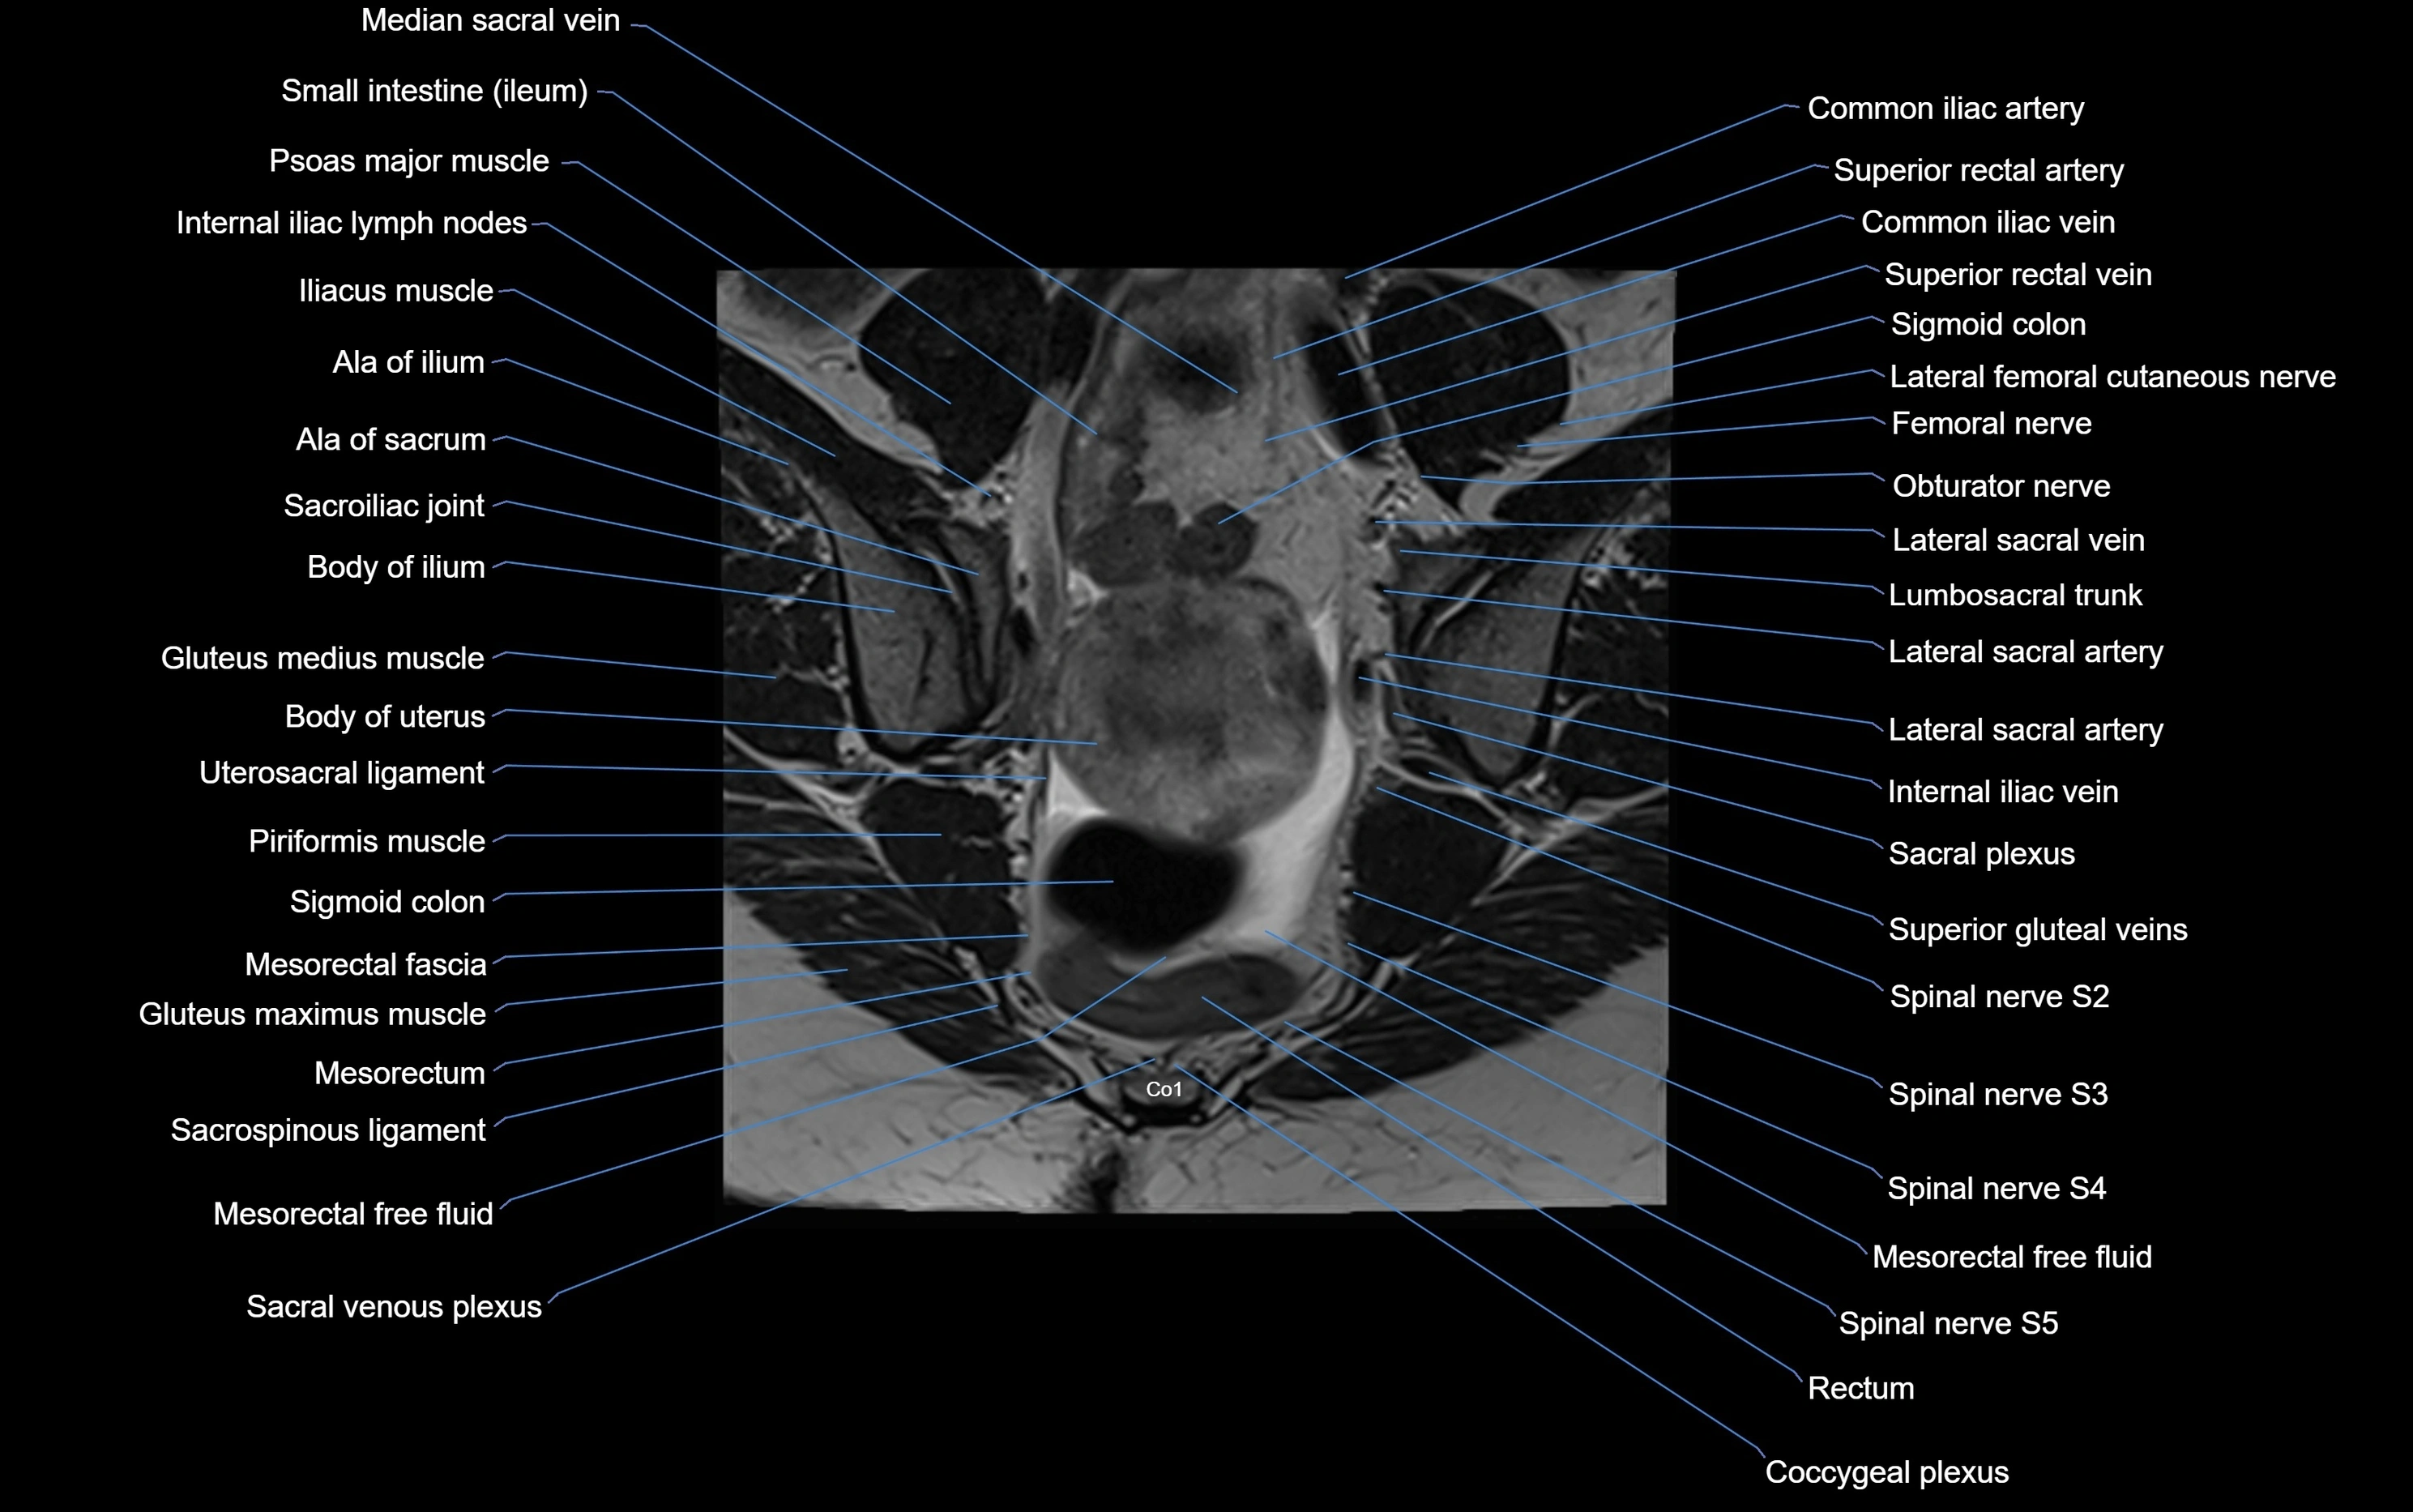

CT image

image